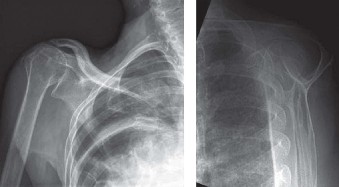

Shoulder CT scans (Answer A) are not typically used to diagnose rotator cuff tears. X-rays, aka roentgenograms (Answer C), can show signs of rotator cuff pathology but are not diagnostic. Some signs of chronic rotator cuff tears that are sometimes seen on AP view x-rays include calcific tendonitis, calcification of the coracohumeral ligament, proximal migration of the humerus, and cystic changes of the greater tuberosity. An outlet view x-ray can show a type III (hooked) acromion, which is correlated with a higher rate of rotator cuff tears, or an OS acromiale, which would require special consideration for surgical treatment. Shoulder arthrograms (Answer D) are used primarily only when MRI is contraindicated and are considered positive for a rotator cuff tear if dye leaks from the glenohumeral joint into the subacromial space. MR arthrogram (Answer E) has been shown to have equivalent diagnostic ability compared with standard MRI and can be used to diagnose rotator cuff tears. However, it adds an additional step and cost to a standard MRI, and it does not offer any additional diagnostic benefit for rotator cuff pathology. Therefore, standard MRI is preferred to MR arthrogram.

Rotator cuff tears are a common reason for shoulder pain and a common reason to obtain shoulder imaging. As a result, numerous different imaging modalities exist offering different pros and cons. Plain films are still the initial imaging modality of choice. These are most useful in ruling out other possible diagnosis but can help with the diagnosis of a rotator cuff tear as well. Changes to the tendon itself

may appear as calcific tendinosis, which would most commonly be seen at the bone–tendon interface. A decrease in the acromiohumeral distance (less than 2 mm) may also be indicative of a cuff tear. In late cases of rotator cuff tears, superior subluxation of the humerus may be evident. Certain variations in acromial anatomy, including spurs or a hook-shaped (type 3) acromions, may be associated with rotator cuff tears as well. With progression of rotator cuff tears, degenerative changes including spurs, cysts, and sclerosis may be evident at the greater tuberosity. In late, massive tears one may see degenerative changes consistent with rotator cuff arthropathy.